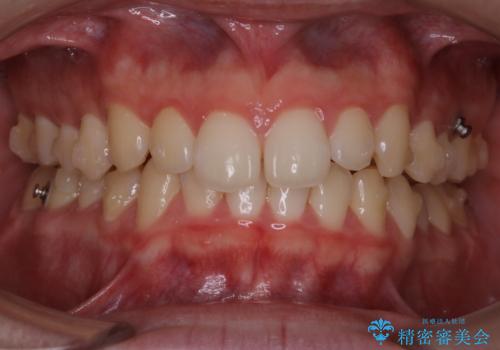

- 上の前歯が見えすぎて気になるとご相談にいらした方です。インビザラインにて前歯の圧下を行うことで歯の見え方の改善し、同時に奥歯の噛み合わせも改善を行いました。

インビザラインを正しく使用して頂けたおかげで、比較的難しいとされる歯の圧下も補助装置を使用せずに行うことが出来ました。上の前歯のラインが整ったことで笑った時の口元の印象を改善させることができ、大変喜んでいただけました。